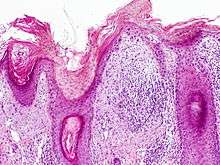

On histologic examination, actinic keratoses usually show a collection of atypical keratinocytes with hyperpigmented or pleomorphic nuclei, extending to the basal layer of the epidermis. A "flag sign" is often described, referring to alternating areas of orthokeratosis and parakeratosis. Epidermal thickening and surrounding areas of sun-damaged skin are often seen.[34] The normal ordered maturation of the keratinocytes is disordered to varying degrees: there may be widening of the intracellular spaces, cytologic atypia such as abnormally large nuclei, and a mild chronic inflammatory infiltrate.[6]

Specific findings depend on the clinical variant and particular lesion characteristics. The seven major histopathologic variants are all characterized by atypical keratinocytic proliferation beginning in the basal layer and confined to the epidermis; they include:[34]

- Hypertrophic: Notable for marked hyperkeratosis, often with evident parakeratosis.[34] Keratinocytes in the stratum malphigii may show a loss of polarity, pleomorphism, and anaplasia.[22] Some irregular downward proliferation into the uppermost dermis may be observed, but does not represent frank invasion.[22]

- Atrophic: With slight hyperkeratosis and overall atrophic changes to the epidermis; the basal layer shows cells with large, hyperchromatic nuclei in close proximity to each other. These cells have been observed to proliferate into the dermis as buds and duct-like structures.[22]

- Lichenoid: Demonstrate a band-like lymphocytic infiltrate in the papillary dermis, directly beneath the dermal-epidermal junction.[34]

- Achantholytic: Intercellular clefts or lacunae in the lowermost epidermal layer that result from anaplastic changes; these produce dyskeratotic cells with disrupted intercellular bridges.

- Bowenoid: This term is controversial and usually refers to full-thickness atypia, microscopically indistinguishable from Bowen's Disease.[22] However most dermatologists and pathologists will use it in reference to tissue samples that are notable for small foci of atypia that involve the full thickness of the epidermis, in the background of a lesion that is otherwise consistent with an AK.[34]

- Epidermolytic: With granular degeneration.[22]

- Pigmented: Show pigmentation in the basal layer of the epidermis, similar to a solar lentigo.[34]